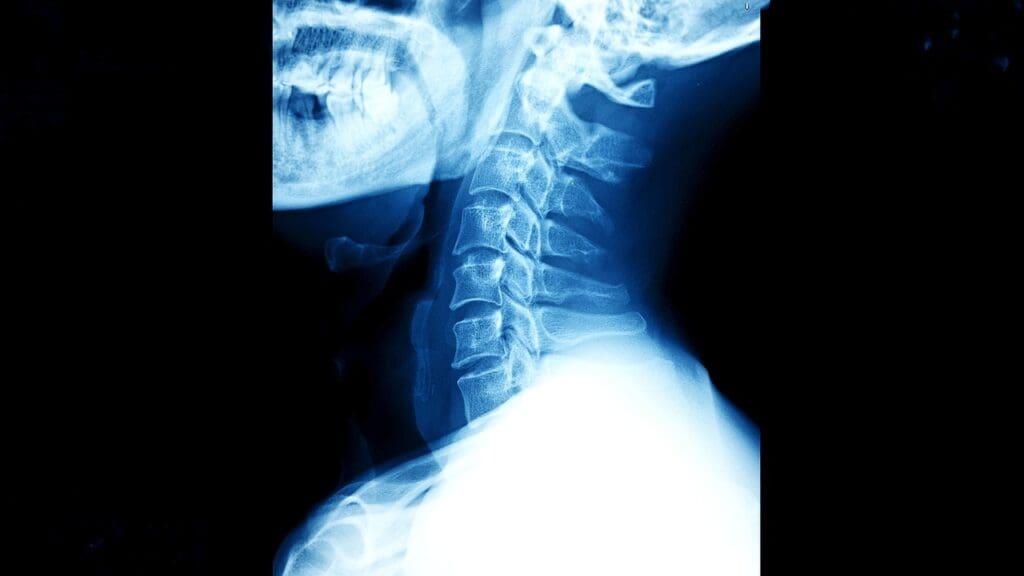

It’s key to know about the cervical spine’s anatomy and function to understand ACDF surgery. The cervical spine, or neck area, supports the head. It also allows for movement and protects the spinal cord and nerves.

The cervical spine has seven vertebrae, from C1 to C7. Between them are intervertebral discs, which act as shock absorbers. These discs help the spine stay flexible. The vertebrae protect the spinal cord, which runs through the spinal canal.

The cervical spine’s design is special. The first two vertebrae (C1 and C2) help with head rotation. The lower vertebrae carry more of the head’s weight.

The cervical spine is vital for head movement. It allows for flexion, extension, rotation, and lateral bending. It also guards the spinal cord and nerve roots.